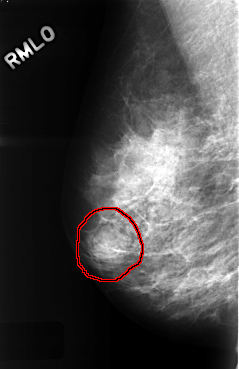

ics_version 1.0 filename C-0333-1 DATE_OF_STUDY 22 12 1995 PATIENT_AGE 44 FILM FILM_TYPE REGULAR DENSITY 2 DATE_DIGITIZED 12 10 1998 DIGITIZER LUMISYS LASER SEQUENCE LEFT_CC LINES 4480 PIXELS_PER_LINE 2904 BITS_PER_PIXEL 12 RESOLUTION 50 NON_OVERLAY LEFT_MLO LINES 4368 PIXELS_PER_LINE 2856 BITS_PER_PIXEL 12 RESOLUTION 50 NON_OVERLAY RIGHT_CC LINES 4456 PIXELS_PER_LINE 2864 BITS_PER_PIXEL 12 RESOLUTION 50 OVERLAY RIGHT_MLO LINES 4424 PIXELS_PER_LINE 2864 BITS_PER_PIXEL 12 RESOLUTION 50 OVERLAY |

FILE: C_0333_1.RIGHT_MLO.OVERLAY TOTAL_ABNORMALITIES 1 ABNORMALITY 1 LESION_TYPE MASS SHAPE LOBULATED MARGINS CIRCUMSCRIBED ASSESSMENT 4 SUBTLETY 4 PATHOLOGY BENIGN TOTAL_OUTLINES 1 BOUNDARY |